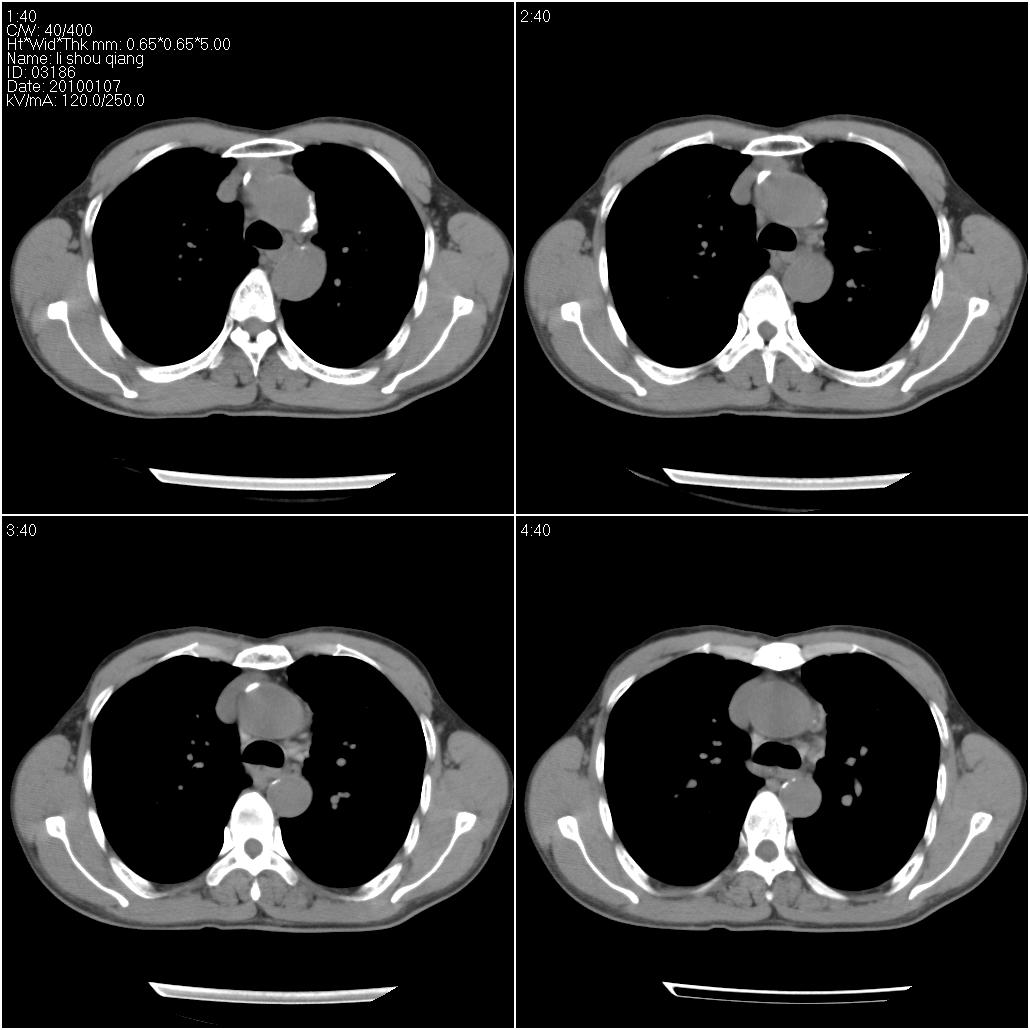

右肺中叶外侧段见一不规则的软组织肿块,边缘可见毛刺,并见厚壁空洞,与胸膜分界欠清。另左下肺见多个小囊状扩张区

右肺中叶周围型肺癌(腺癌)并非空洞而是空泡症

右肺中叶外侧段可见团块影,外形不规则,内见空泡征。左下肺见蜂窝状低密度透亮影,部分层面主动脉旁瘤样突出。考虑右肺中叶外围型肺癌可能性大,左下肺支气管扩张,主动脉弓瘤样突出。

炎性假瘤,右肺中叶周围型肺癌(腺癌)并非空洞而是空泡症。

1、右肺中叶周围型肺癌(内空泡)。

2、左肺下叶支扩,不除外合并肺囊肿。

3、建议冠状位重建除外主动脉弓息室样动脉瘤。